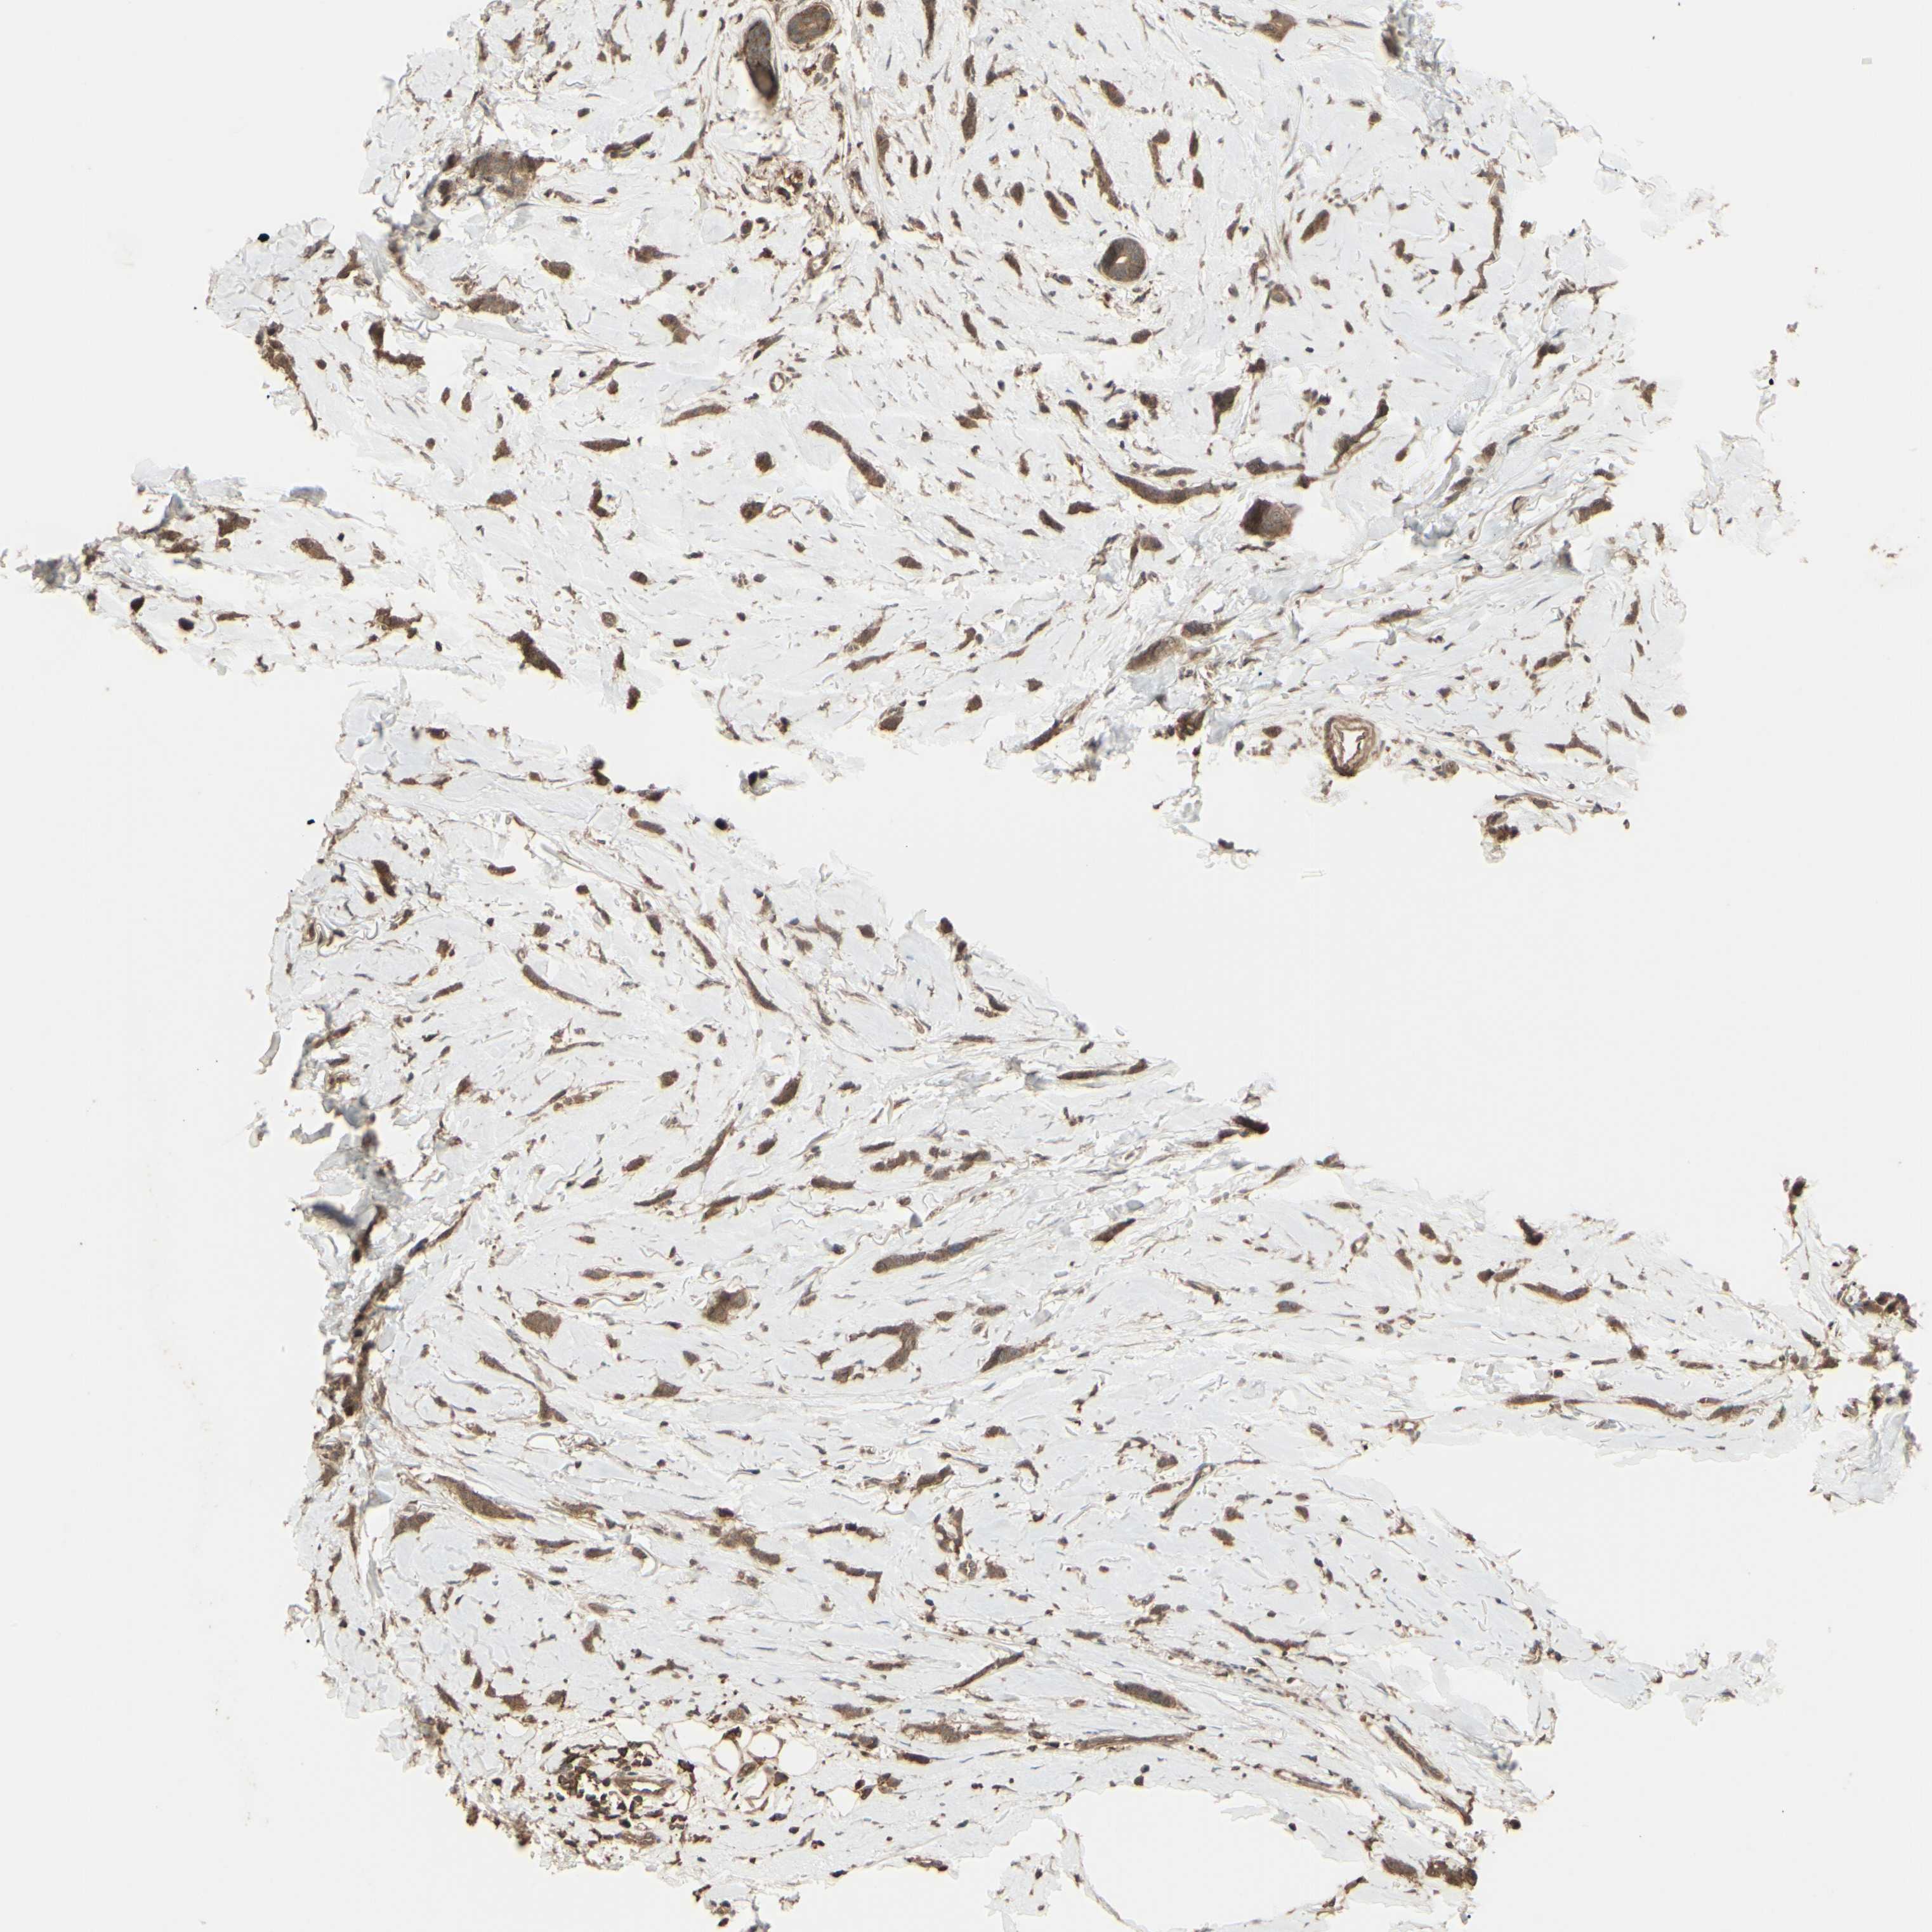

CANCER BREAST CANCER Show tissue menu

BRCA TCGA BRCA VALIDATION PROTEIN EXPRESSION